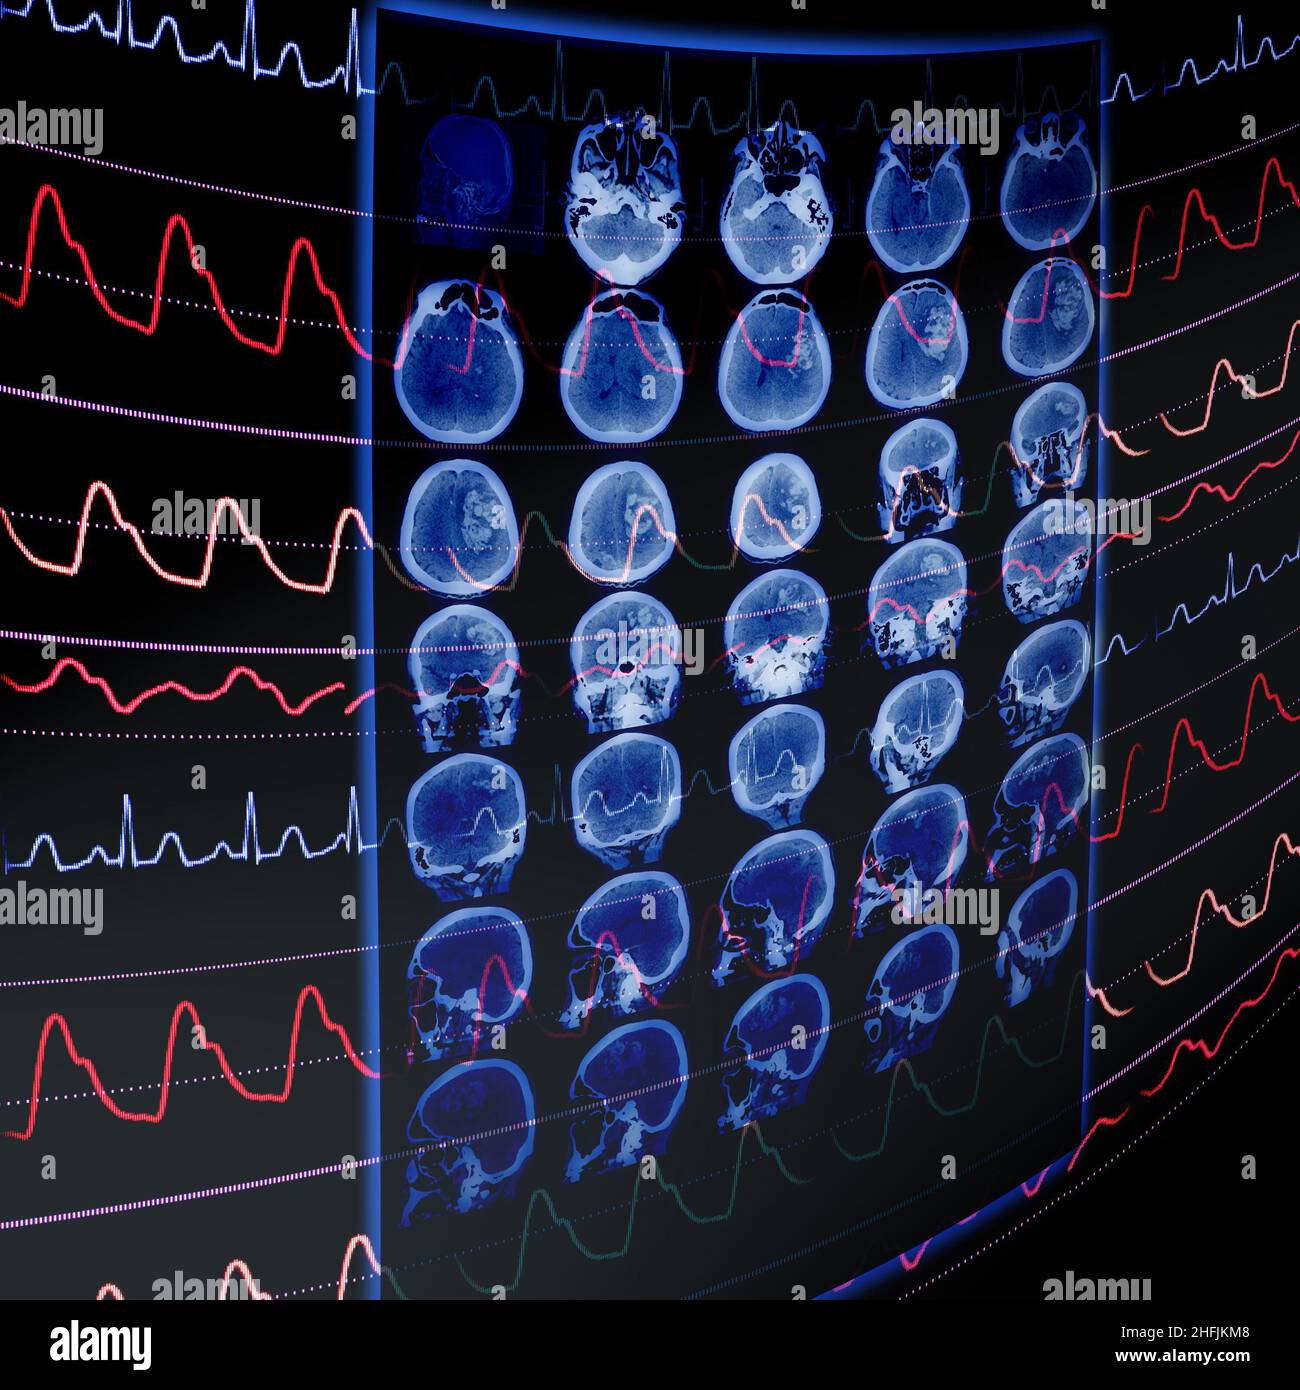

CT film and ECG monitoring as a medical concept of early vascular disease detection. Stock Photohttps://www.alamy.com/image-license-details/?v=1https://www.alamy.com/ct-film-and-ecg-monitoring-as-a-medical-concept-of-early-vascular-disease-detection-image457100008.html

CT film and ECG monitoring as a medical concept of early vascular disease detection. Stock Photohttps://www.alamy.com/image-license-details/?v=1https://www.alamy.com/ct-film-and-ecg-monitoring-as-a-medical-concept-of-early-vascular-disease-detection-image457100008.htmlRF2HFJKM8–CT film and ECG monitoring as a medical concept of early vascular disease detection.